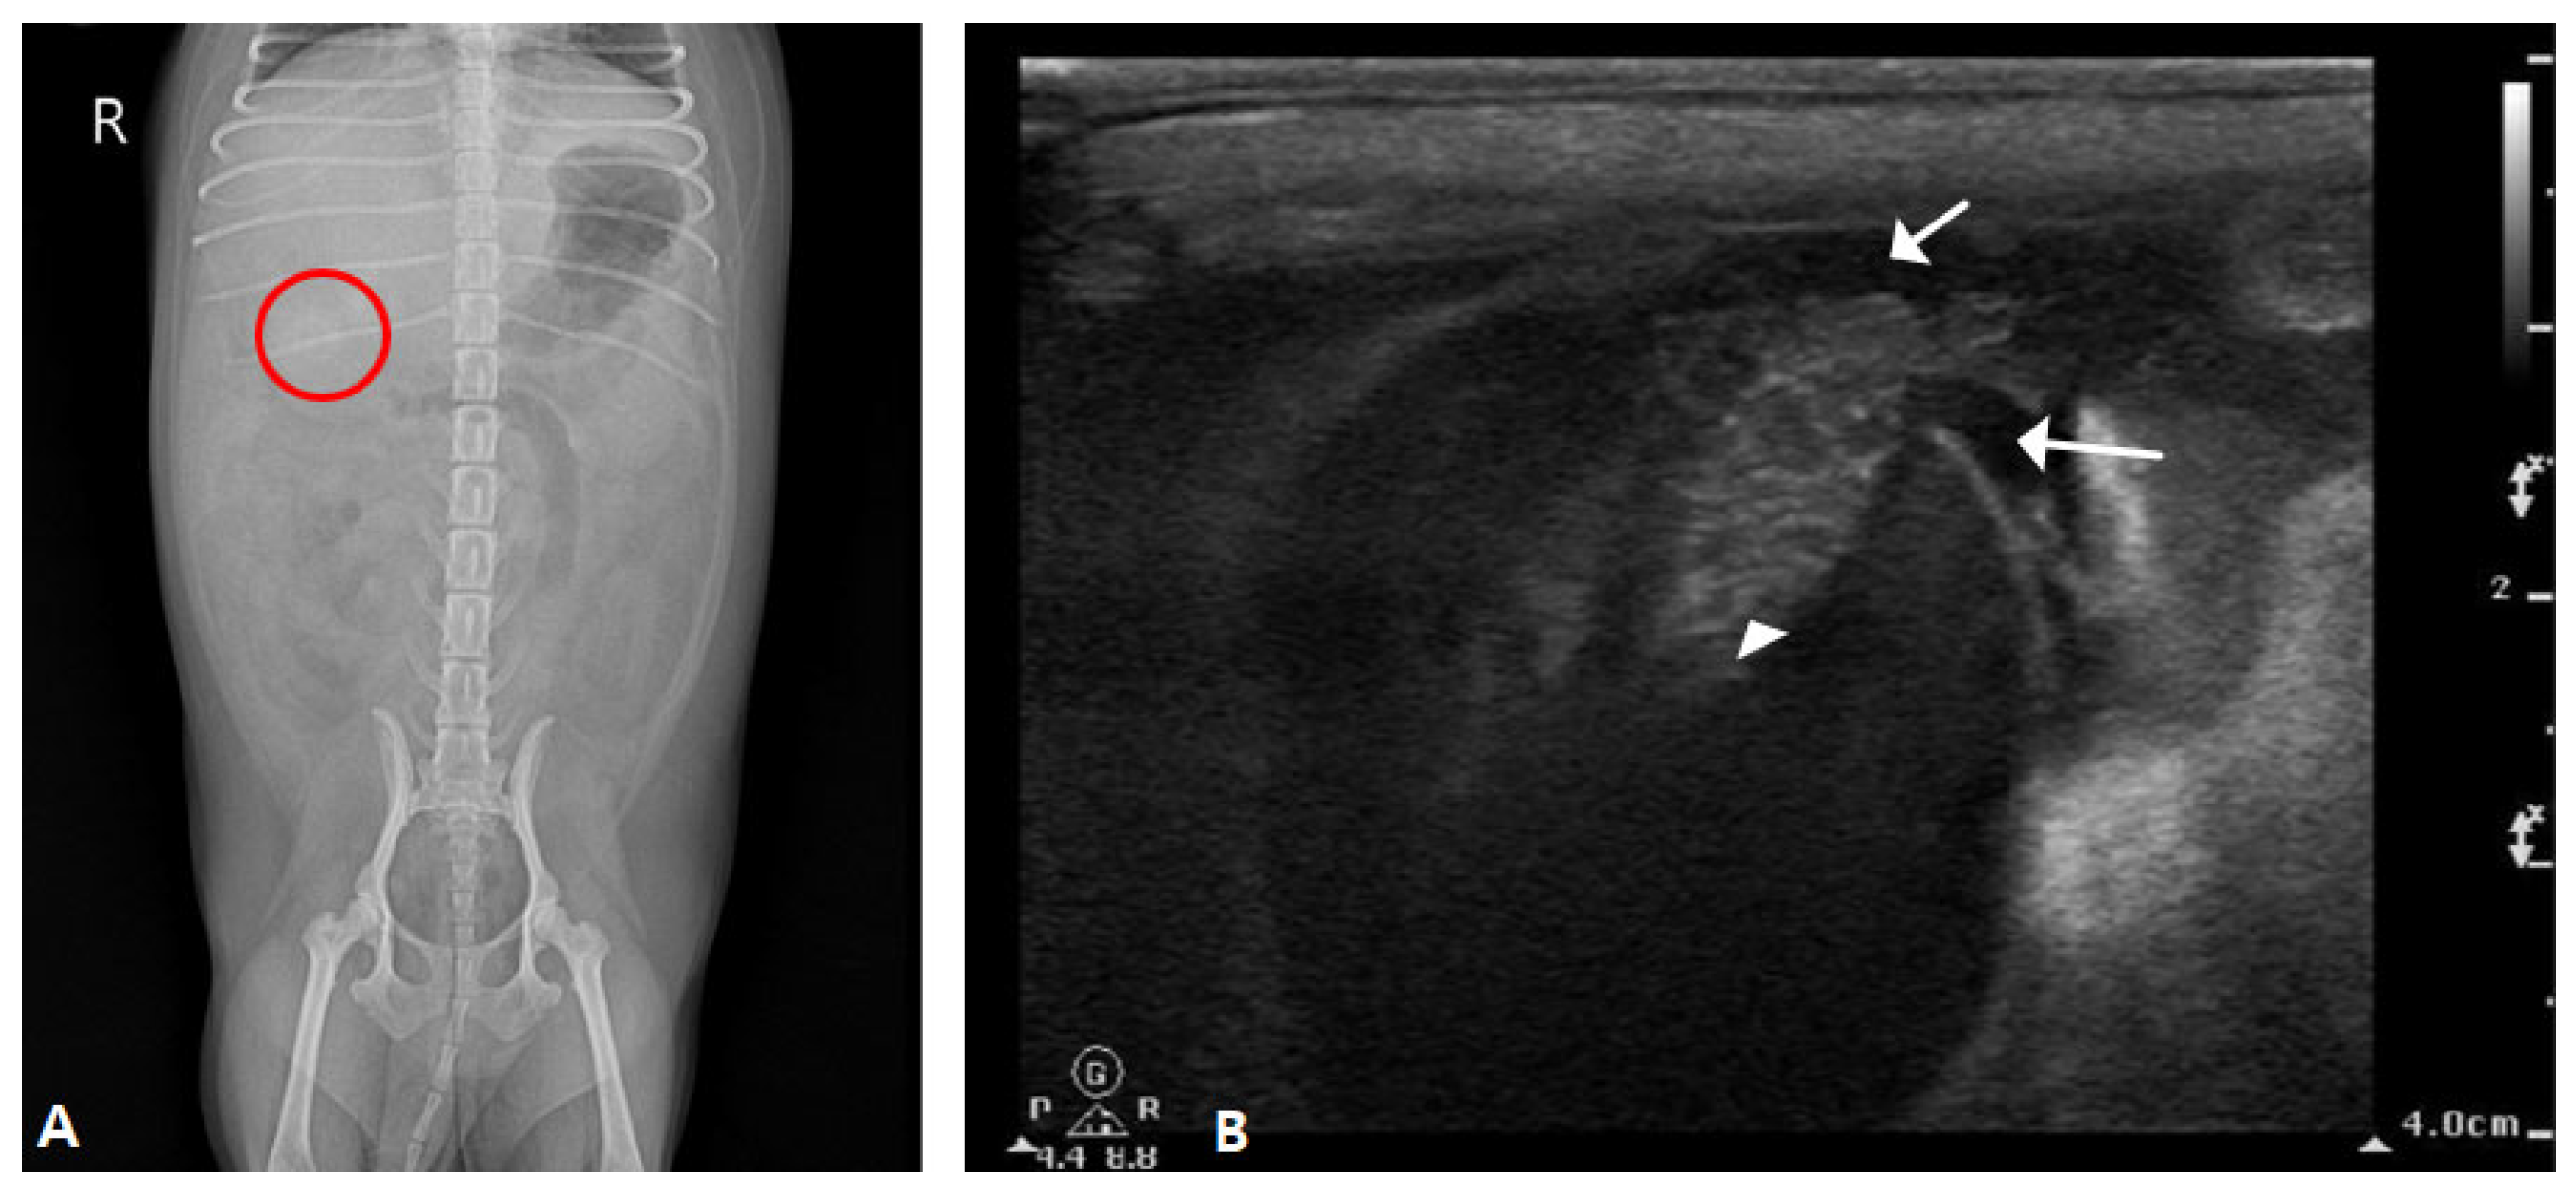

Abdominal radiography revealed mineralized radiopaque substances in the right upper abdomen (Figure 4A). Abdominal ultrasonography revealed dilatation of the gallbladder with an irregular, immobile substance inside the gallbladder that penetrated the ruptured gallbladder wall. In addition, a large amount of echogenic ascites were confirmed around the gallbladder, fat thickening was confirmed, and peritonitis was suspected (Figure 4B).

Figure 4.

Radiography and sonography of the gallbladder. (A) An opaque material with rounded margins was identified in the right upper abdomen (round circle). (B) Hyperechoic round-shaped immobile sludge inside the gallbladder penetrated the abdominal gallbladder wall (arrowhead) and spanned the wall, and free fluid was identified around the gallbladder (arrow).